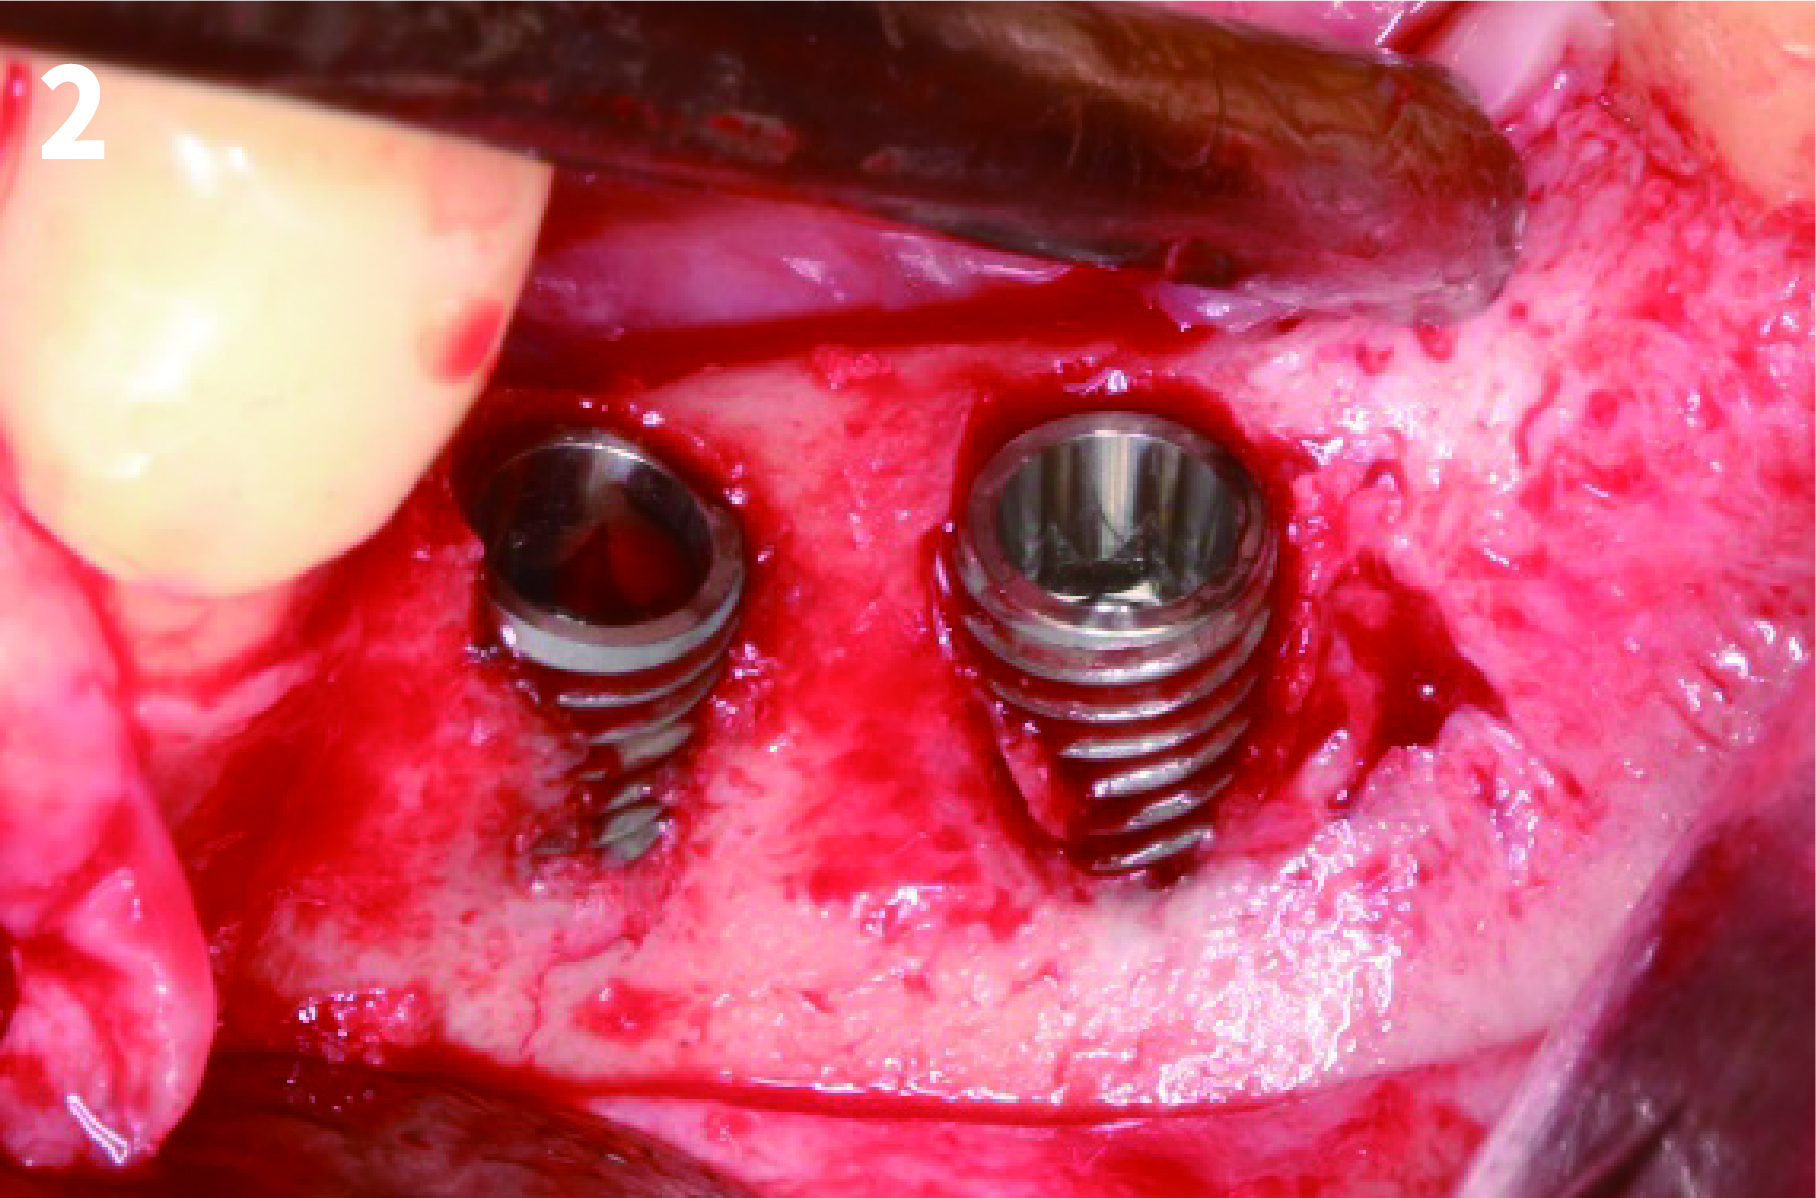

Case 1: Simply Augmented Severe Dehiscence Defect on Anterior Area

2. After exposure the bony defect with mucoperiosteal flap, completely remove the granulation tissue, inflammatory tissue.